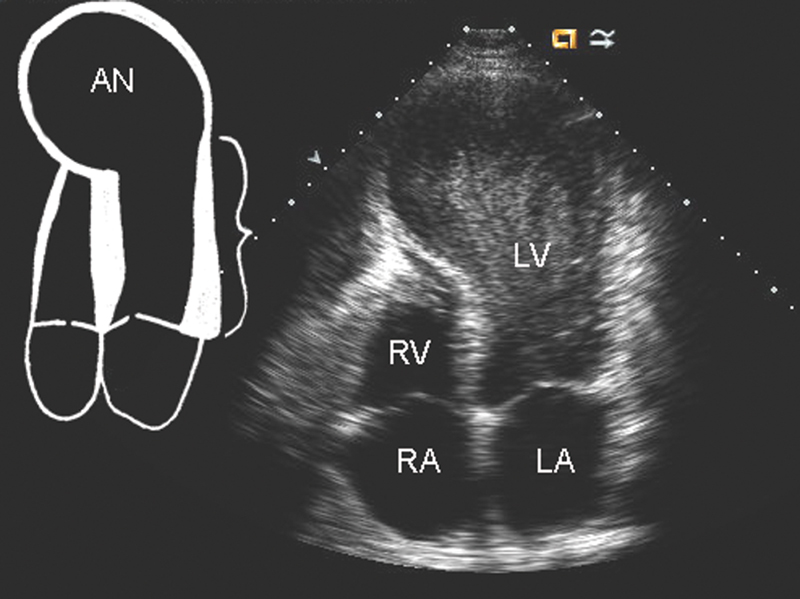

فحوصات تشخيصية لبعض امراض القلب والشرايين التاجية